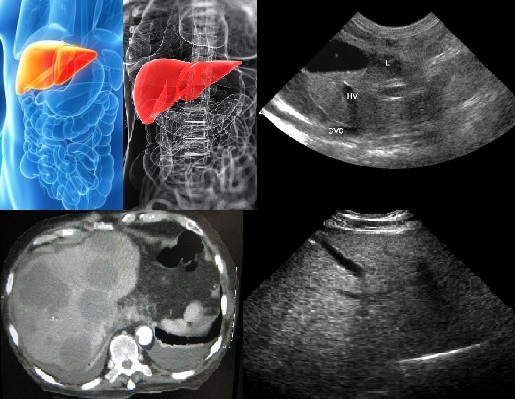

- Проведение ультразвукового исследования позволяет выявить эхопризнаки заболевания. При осмотре анализируется структура печени, очертания границ, состояние кровеносных сосудов. Отклонения от нормы эхоскопически визуализируются:

- острый гепатит – увеличение правой части печени со снижением эхогенности;

- хронический гепатит – разрастание органа за счёт левой части. Границы печени неровные, повышенная эхогенность;

- эхографические признаки цирроза – неравномерное изменение эхогенности.

- КТ – компьютерная томография.

- МР-томография.

Наиболее информативными являются такие методы: УЗИ, КТ и МРТ.